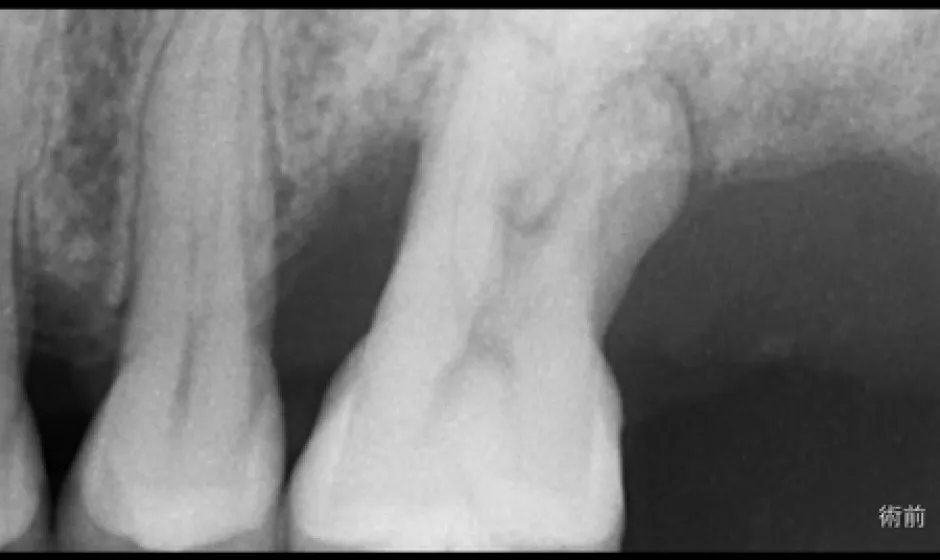

01精密根管治療

「抜くしかない」と言われた歯でも、根の中の感染を適切に抑えられる治療技術があれば、歯を残せる可能性があります。根管は非常に細く複雑で、わずかな取り残しが痛みや腫れの再発につながることもあるため、当院では必要に応じてCTやマイクロスコープを活用し、原因を見極めながら丁寧に処置を進めます。

大杉歯科医院が大切にしているのは、早く終える治療ではなく、歯を守る治療。津市で、できるだけ天然歯を残したい方の選択肢になれるよう取り組んでいます。症例1

- 治療名

- マイクロスコープとラバーダムを使用した精密根管治療

- 患者様

- 30代男性

- 執刀医

- Dr. 大杉

- 治療期間

- 3ヶ月

- 治療費

- 精密根管治療:130,000円(税込)

築造:40,000円(税込) - リスク

- 治療中〜治療後に痛みが出る場合あり

再感染・治癒不全の可能性

補綴後も定期管理が必要